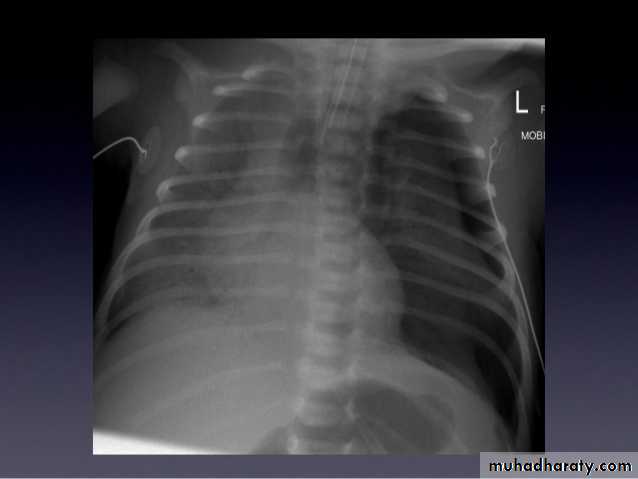

79.Diaphragmatic hernia

congenital cystic adenomatous malformationSoap bubble appearance in the left hemithorax with shifting of mediastinum to the right

Left hemidiaphram cannot be seen

Presence of nasogasric tube

Soap bubble appearance in the left hemithorax with air fluid level

Shifting of mediastinum to opposite side